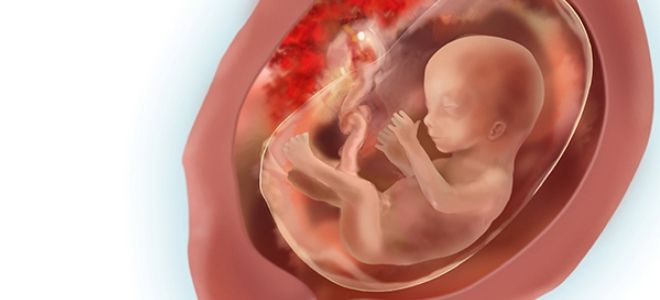

На 16-й неделе беременности малыш начинает активно развиваться. В этот период формируется его маленькое личико. Во время ультразвукового исследования врач может увидеть глазки, уши, рот, брови и ресницы. Кожа плода все еще имеет красноватый оттенок и множество складок. Скелет растет стремительно, что способствует выпрямлению тела. Голова становится более пропорциональной по отношению к туловищу.

На 16-й неделе беременности развитие плода вступает в новую стадию. Хрящевая ткань начинает постепенно заменяться костной, что является важным этапом в формировании скелета. Мышечная ткань становится более развитой, что позволяет ребенку проявлять активность в материнской утробе. Он начинает активно двигать руками и ногами, открывать и закрывать рот, а также поворачивать голову в разные стороны. В этот период начинают функционировать такие органы и системы, как почки, печень и мочевой пузырь. К 16 неделе у малыша уже работают органы желудочно-кишечного тракта, сердце и кровеносная система.